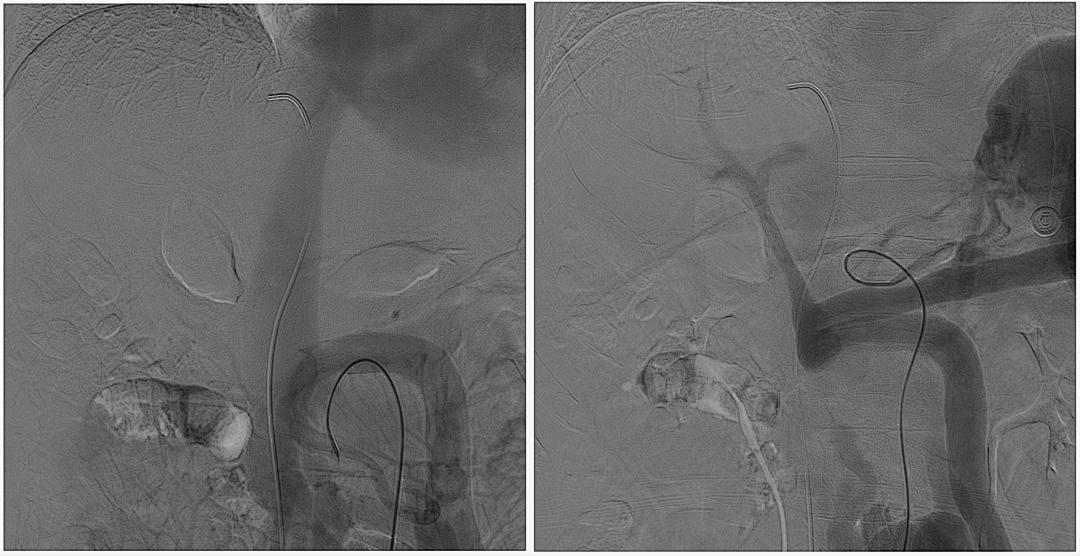

至肠系膜上动脉行间接门静脉造影,未见门静脉显影,可见巨大异常分流道,遂至脾动脉行间接门脉造影可见门静脉异常纤细,肠系膜下静脉见异常分流道形成

以微导管行肝动脉标记辅助穿刺,门静脉造影显示血流呈离肝状态

超选至肠系膜下静脉异常分流道,予以栓塞18mm的Amplatzer vascular plug及适量25%生物胶,造影示异常分流道消失

8mm覆膜支架释放于肝内穿刺道,考虑门脉纤细,遂以6mm球囊后扩张